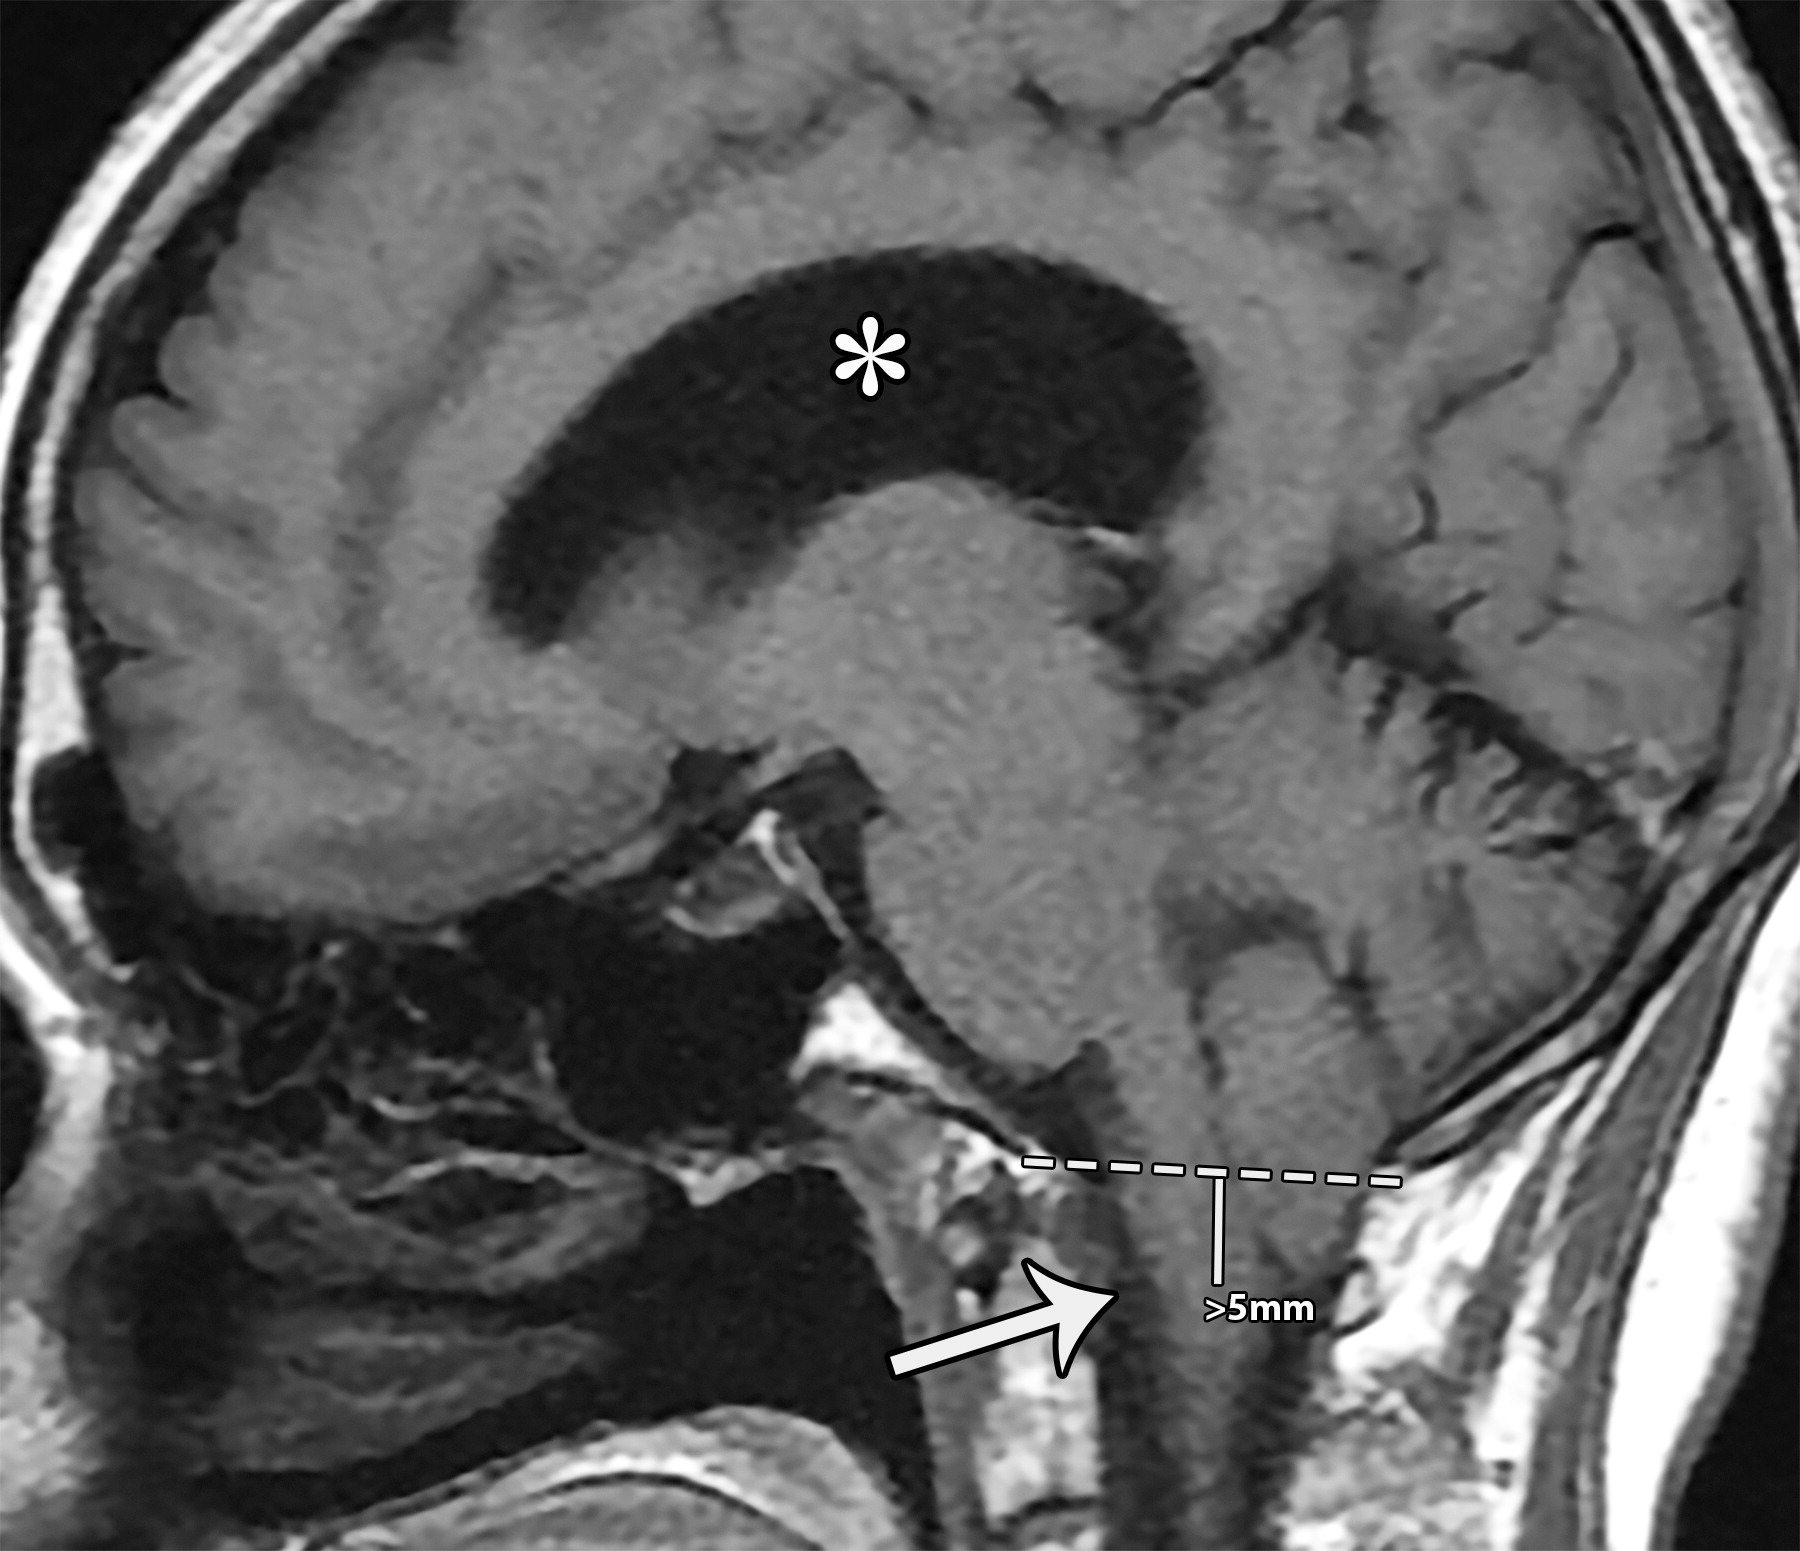

04195f077fedbc1c48a7bdd1f903932f.jpeg

相比于McRae线(白色虚线),小脑扁桃体向下移位(超过5毫米),注意枕大池闭塞,延髓向前移位(白色长箭头)以及脑积水(白色*)